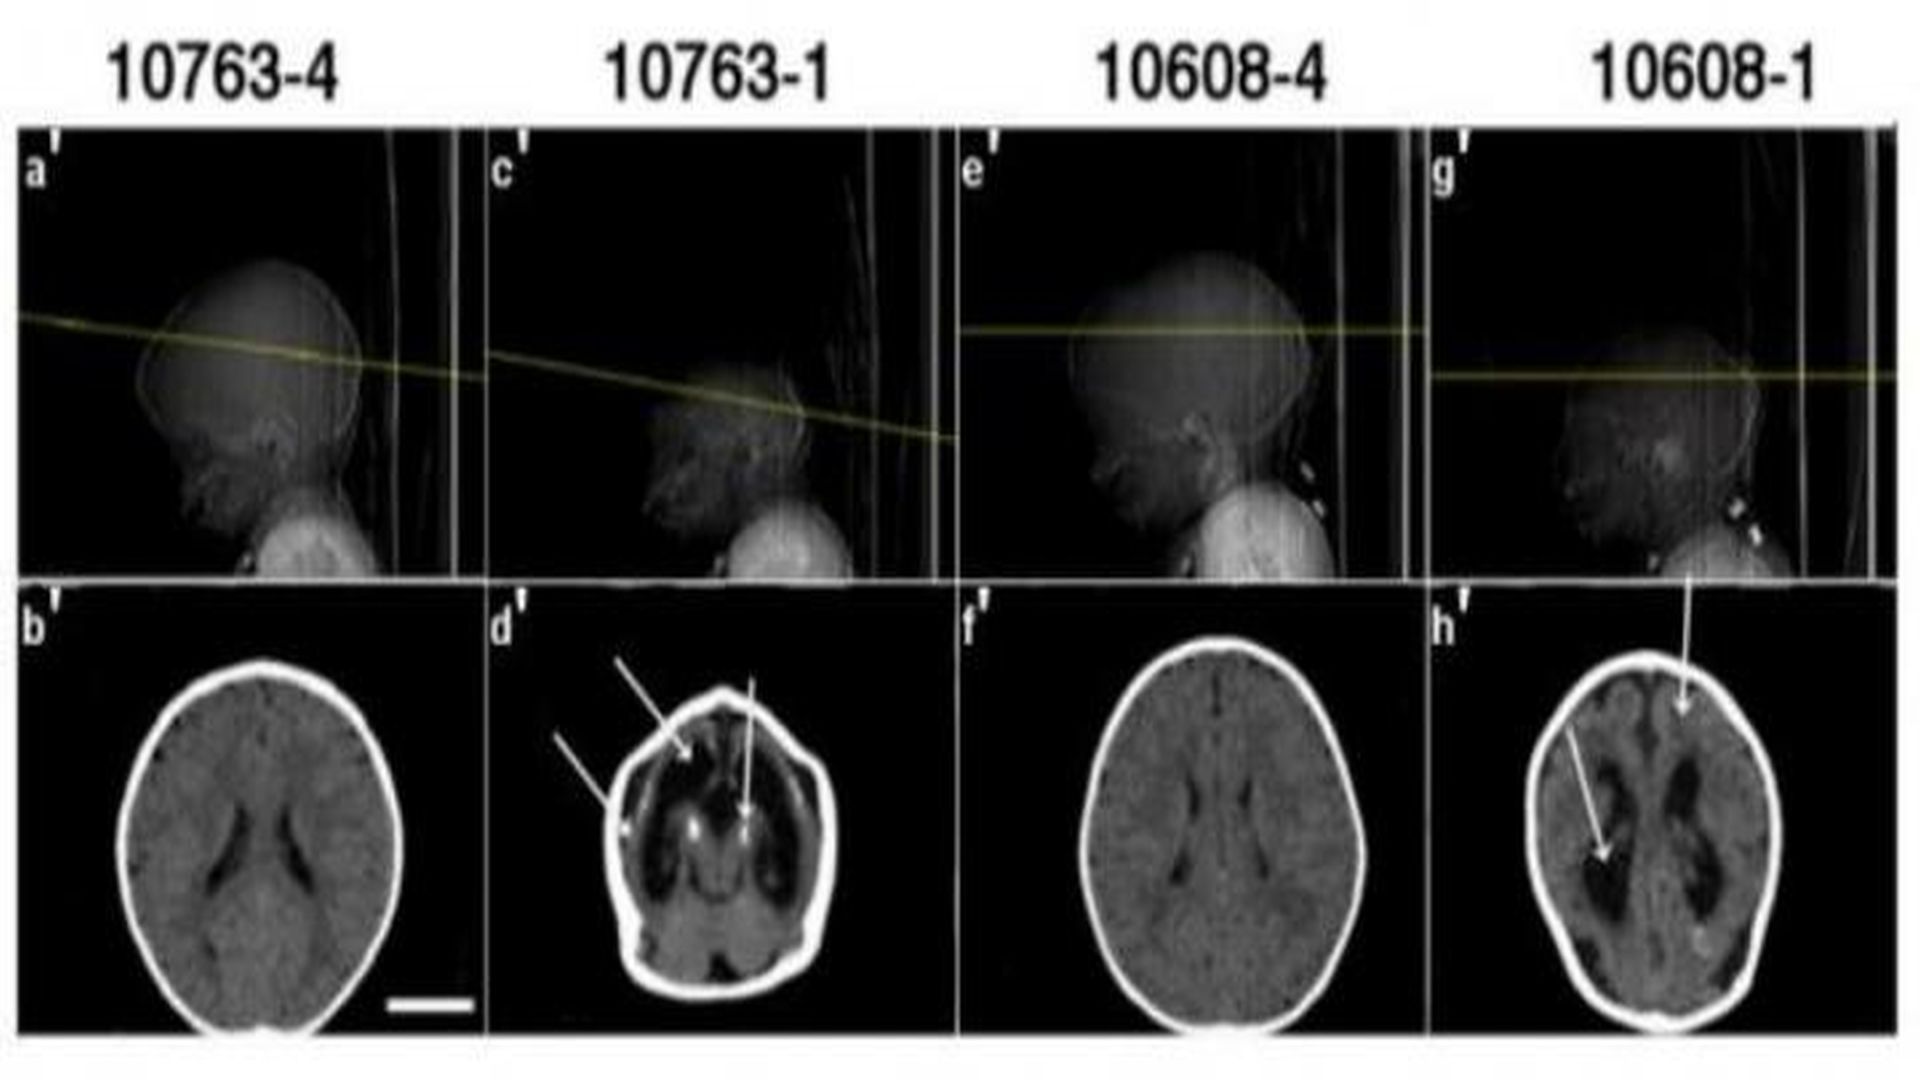

Computed tomography scans from two pairs of twins participant in the study show typical abnormalities (second and forth images) associated with congenital Zika syndrome and microcephaly. Courtesy of HUG-Cell